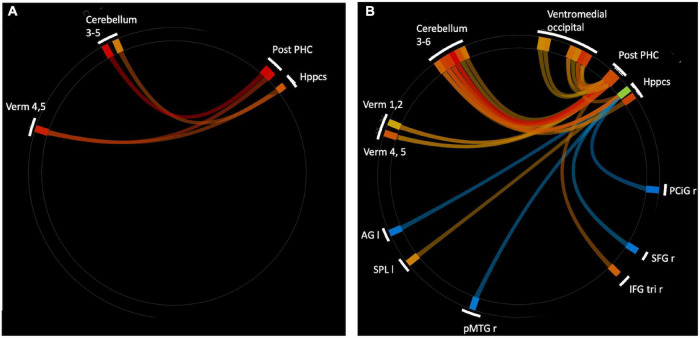

To expand on this finding, we next performed an analysis using the CONN built-in ROI atlas of 164 brain regions, based on the Harvard-Oxford atlas for cortical and subcortical regions, and the Automated Anatomical Labeling (AAL) atlas for cerebellar subregions. In this analysis, we chose six a priori seed regions consisting of bilateral hippocampus, posterior parahippocampal cortex (pPaHC), and anterior parahippocampal cortex (aPaHC). ROI-to-ROI analyses take the mean resting brain activity across all the voxels within each anatomically defined source ROI and correlates this with the mean brain activity across voxels in each anatomically defined target ROI. Consistent with our seed-to-voxel analysis, we found stronger connectivity with anterior cerebellum (lobules III and IV/V and vermis IV/V; Figure 2 and Table 2).

TABLE 2: Significantly altered connections comparing aged users vs. aged non-users in an ROI to ROI analysis, using bilateral anterior parahippocampus, bilateral posterior parahippcampus (pPaHC), and bilateral hippocampus as seed regions.

| Parahippocampal Gyrus, posterior division Left | Cerebellum 4 5 Left | 4.79 | 0.0004 |

| Parahippocampal Gyrus, posterior division Right | Vermis 45 | 3.93 | 0.016 |

| Hippocampus Left | Vermis 45 | 3.52 | 0.049 |

| Hippocampus Left | Cerebellum 3 Left | 3.43 | 0.049 |

All altered connections are users > non-users. Statistics shown are FWE corrected at the seed level. R, right; L, left; Cerebellum 45, Cerebellar lobules IV/V; Vermis 45, Vermis IV/V; Cerebellum 3, Cerebellar lobule III.

In order to determine which pattern of connectivity might be more typical of the older adult brain, we next examined brain connectivity in these same regions comparing older adult non-users and the sample of younger adult non-users between the ages of 25 and 35 (n = 43, mean 28.9 years, sd 3.1). Our goal was to determine whether the brain connectivity differences observed in older users vs. non-users were consistent with a profile of accelerated aging, decelerated aging, or neither. We conducted an ROI-to-ROI analysis using bilateral hippocampus and anterior and posterior hippocampal cortex as the source regions and contrasted older non-users and younger non-users (n = 23, 52.2% female, Supplementary Table 1), using seed-based FDR-corrections as above. We found that, relative to older non-users, younger non-users had significantly stronger rsFC between pPaHC and anterior cerebellum (cerebellar lobules III and IV/V, vermis IV/V), similar to the stronger rsFC in older users vs. older non-users. Younger non-users also had significantly stronger rsFC between hippocampus and anterior cerebellum (cerebellar lobules III and IV/V, vermis IV/V). Thus, rsFC involving cerebellar lobules IV/V were particularly influenced by age, with strengthened rsFC to bilateral hippocampus, pPaHC, and aPaHC. There were also several altered connections between the source regions and ventromedial occipital cortex (Figure 2 and Table 3).